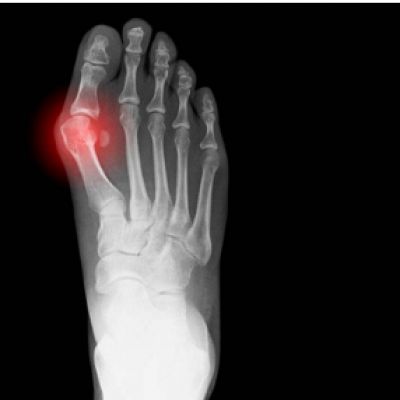

大脚骨在医学上称为“拇外翻”,是足踝疾病中比较常见的一种,是指大拇趾向外倾斜大于生理角度15度的一种畸形症状。最常造成的问题就是足部的疼痛和穿鞋受限,严重的还会出现骨性关节炎,造成关节受损,影响行走功能。

拇外翻俗称“大脚骨”“脚孤拐”,主要表现为拇趾向外侧偏斜,并随着时间的推移,症状逐渐加重,影响脚步美观,影响日常行走活动。很多人对大脚骨的认知还比较模糊,也就导致了在选择治疗方式时的盲目选择。